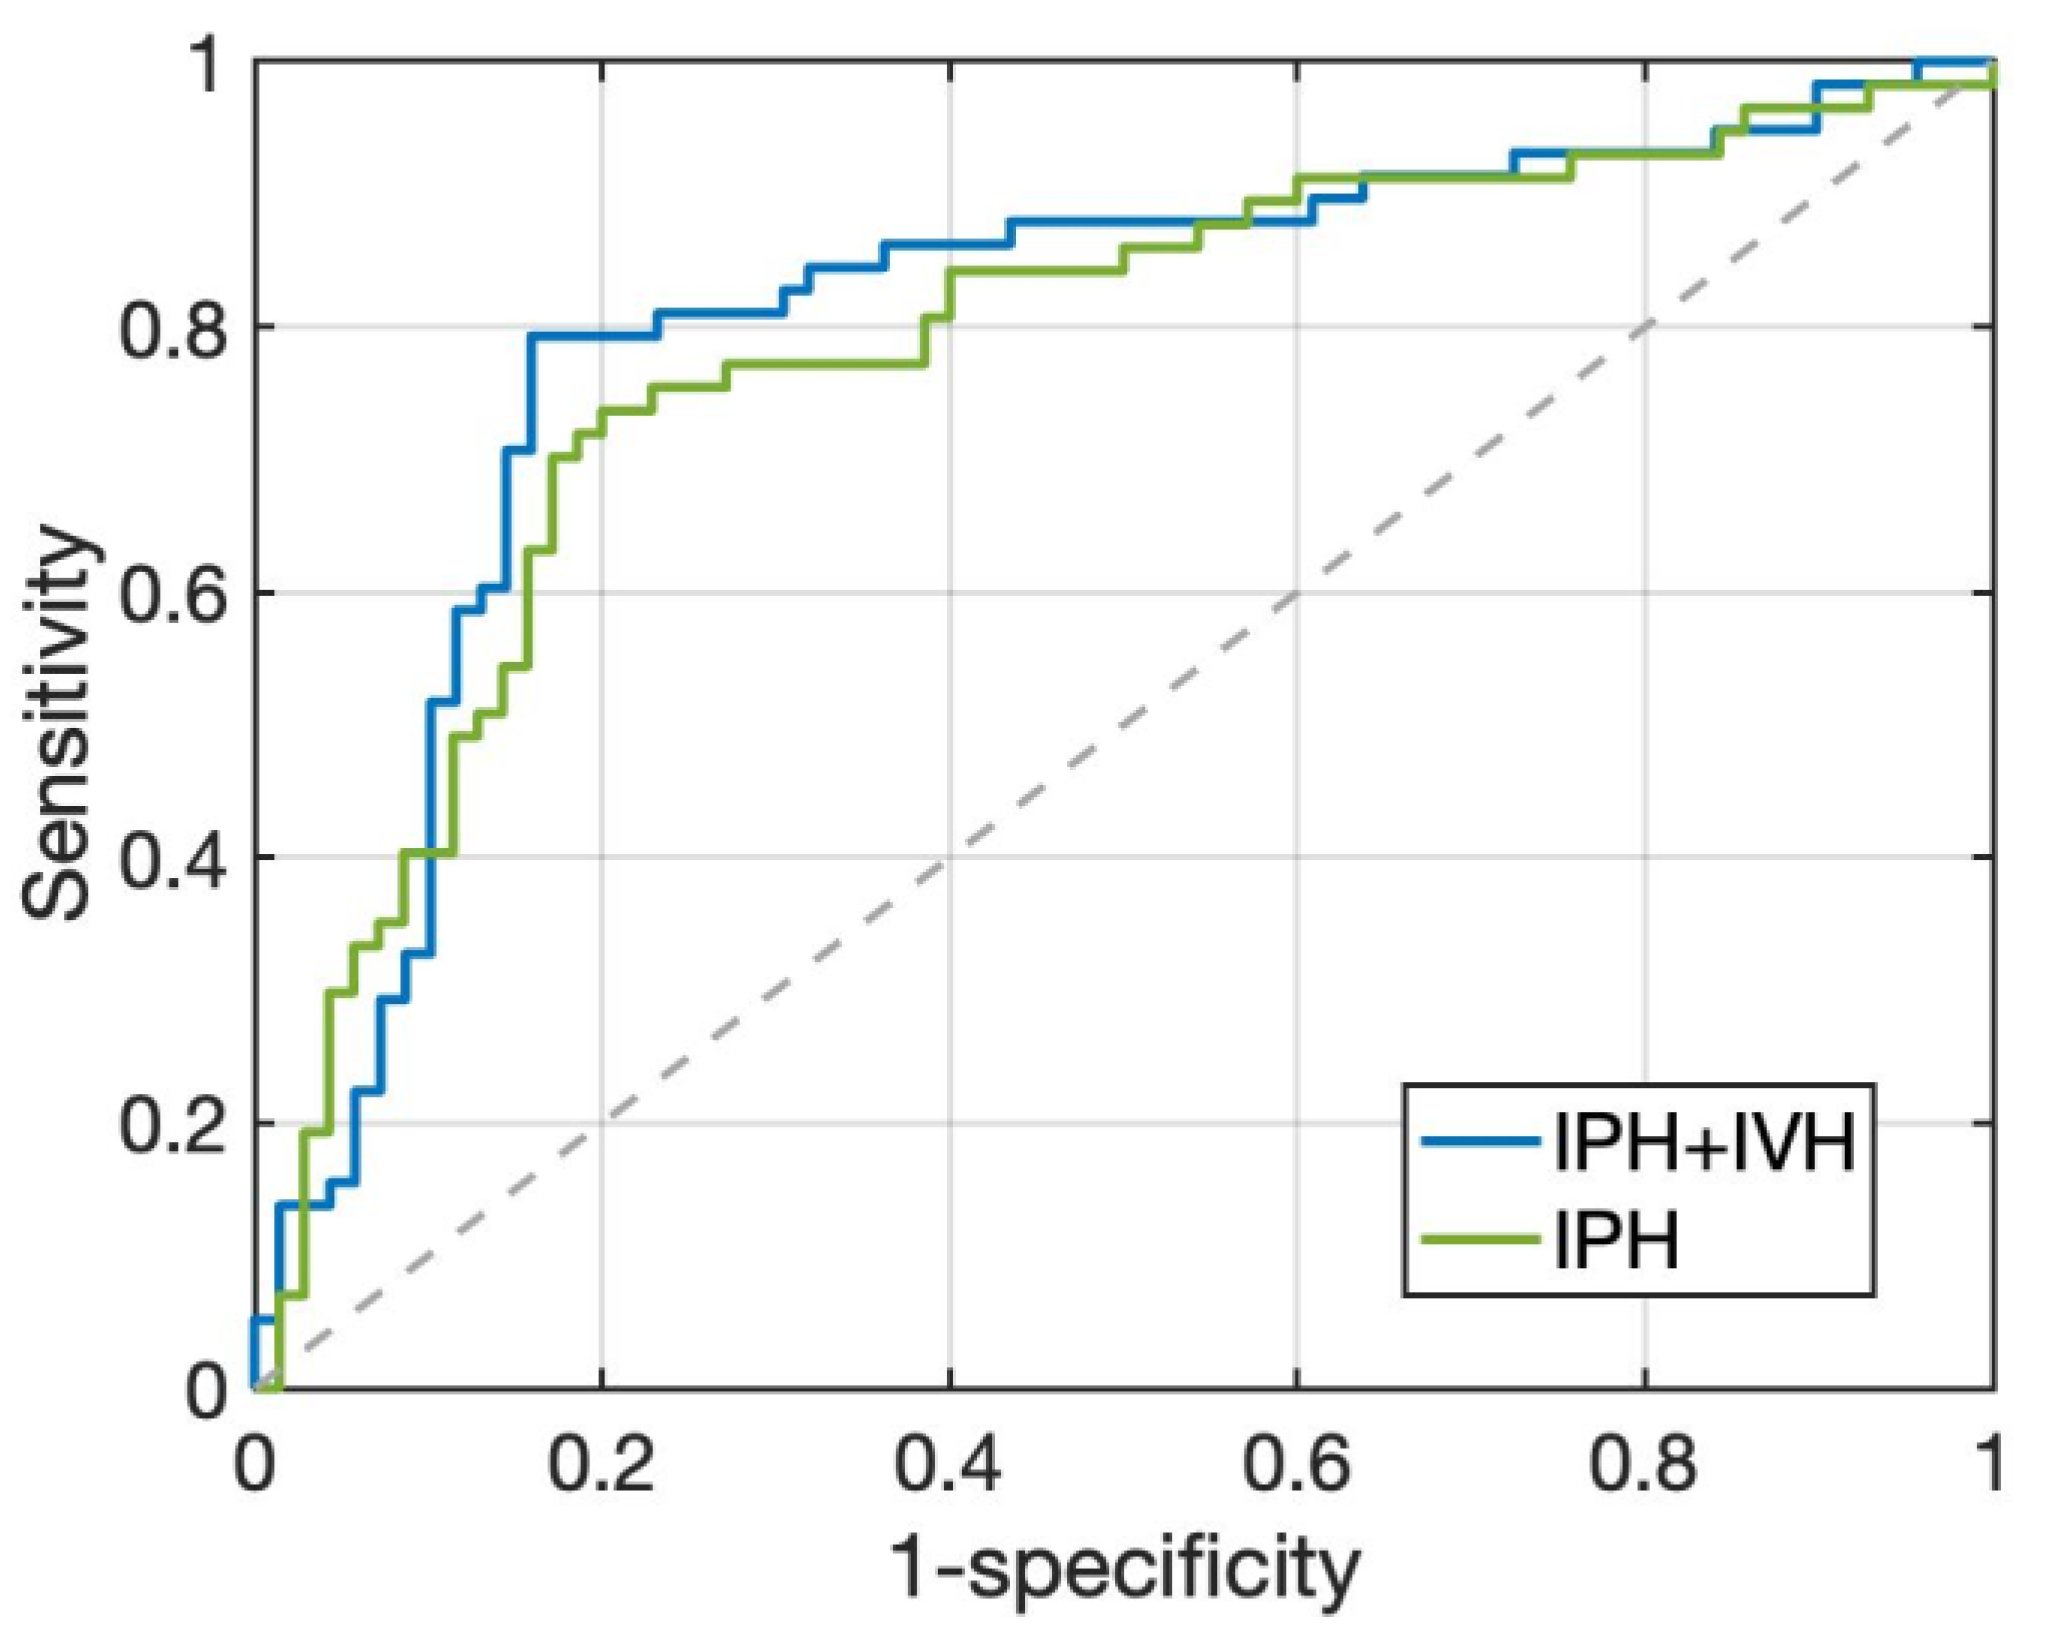

3.3. HE Prediction Performance of Two Radiomics Models

3.4. Radiologic Parameters and Early Outcome of Two Radiomics Models